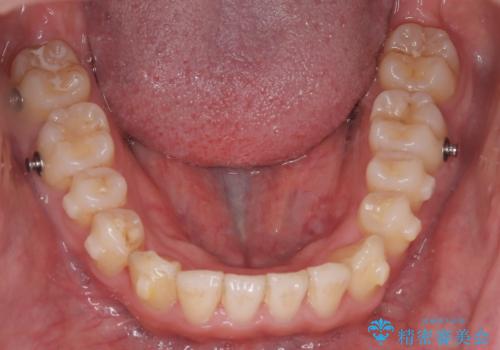

今回は臼歯部の遠心移動を行うために2級ゴムを使用しています。

歯列の幅が狭かったため、横に広げながらスペースを作り、叢生の改善を行いました。

左側の犬歯関係も治療前より良い状態で治療を完了することができました。